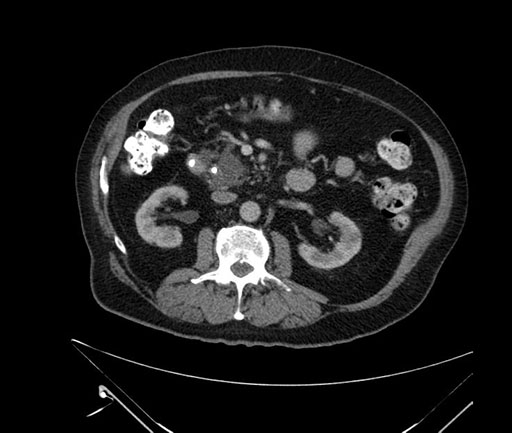

Axial - stented